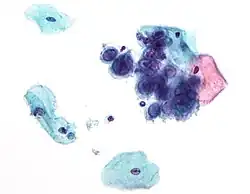

Некоторые вирусы не вызывают никаких видимых изменений в поражённой клетке. Клетки, в которых вирус находится в латентном состоянии и неактивен, имеют мало признаков инфекции и нормально функционируют[122]. Это является причиной хронических инфекций, и вирус при них может никак себя не проявлять многие месяцы или годы. Так часто бывает, например, с вирусом герпеса[123][124]. Некоторые вирусы, например вирус Эпштейна — Барр, могут вызывать быстрое размножение клеток без появления злокачественности[125], в то время как другие, такие как папилломавирусы, могут вызвать рак[126].

Злокачественные опухоли

Вирусы могут вызывать злокачественные новообразования (в частности, гепатоцеллюлярную карциному или саркому Капоши) у человека и других видов, хотя они возникают лишь у небольшой части инфицированных. Опухолеродные вирусы относятся к различным семействам; они включают и РНК-, и ДНК-содержащие вирусы, поэтому единого типа «онковирус» не существует (устаревший термин, первоначально применявшийся для быстро трансформирующихся ретровирусов). Развитие рака определяется множеством факторов, такими как иммунитет хозяина[181] и его мутации[182]. К вирусам, способным вызывать рак у человека, относят некоторых представителей папилломавируса человека, вируса гепатита B и C, вируса Эпштейна — Барр, герпесвируса саркомы Капоши и человеческого T-лимфотропного вируса. Совсем недавно открытым вирусом рака человека является полиомавирус (полиомавирус клеток Меркеля), который в большинстве случаев вызывает редкую форму рака кожи, называемого карциномой клеток Меркеля[183]. Вирусы гепатита могут вызвать хроническую вирусную инфекцию, которая приводит к раку печени[184][185]. Заражение человеческим T-лимфотрофным вирусом может привести к тропическому спастическому параперезу и зрелой лейкемии Т-клеток[186]. Человеческие папилломавирусы могут вызывать рак шейки матки, кожи, ануса и полового члена[187]. Из герпесвирусов герпесвирус саркомы Капоши вызывает саркому Капоши и лимфому полости тела, вирус Эпштейна — Барр — лимфому Беркитта, лимфогранулематоз, нарушения B-лимфопролиферации и назофарингеальную карциному[188]. Полиомавирус клеток Меркеля близок к вирусу SV40 и полиомавирусам мышей, которые более 50 лет использовались как животные модели для изучения вирусного рака[189].